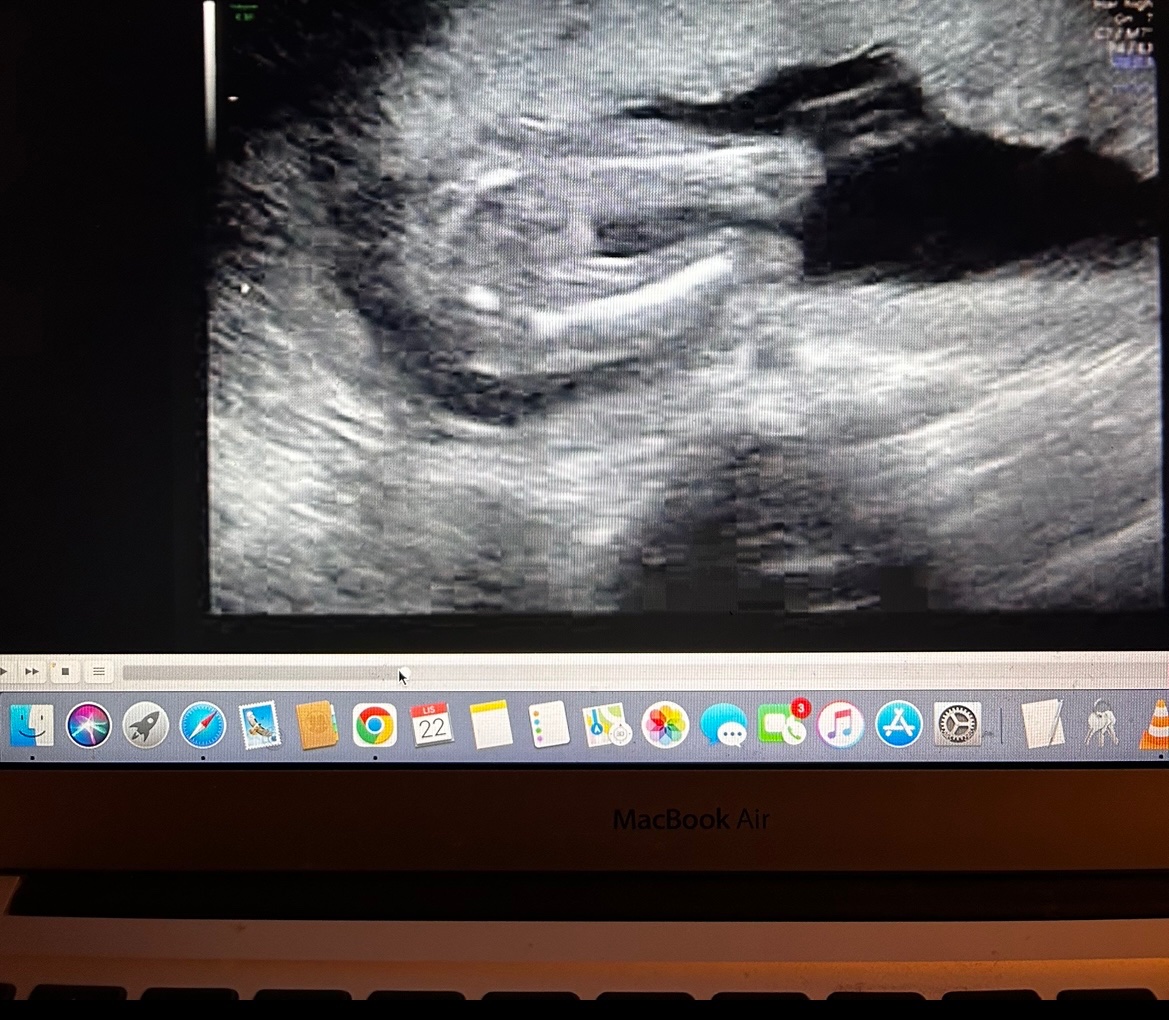

Holčička nebo chlapeček? Co vidíte na obrázku?

Dobrý večer všem, co vidíte? Díky za názory 🙂

Já tyhle dotazy asi nechápu. Fotky ti udělal asi gynekolog, ne? On to z utz nepoznal, že se ptáš tady? Nebo ti řekl pohlaví, ale ještě si to musíš ověřit?

Holka